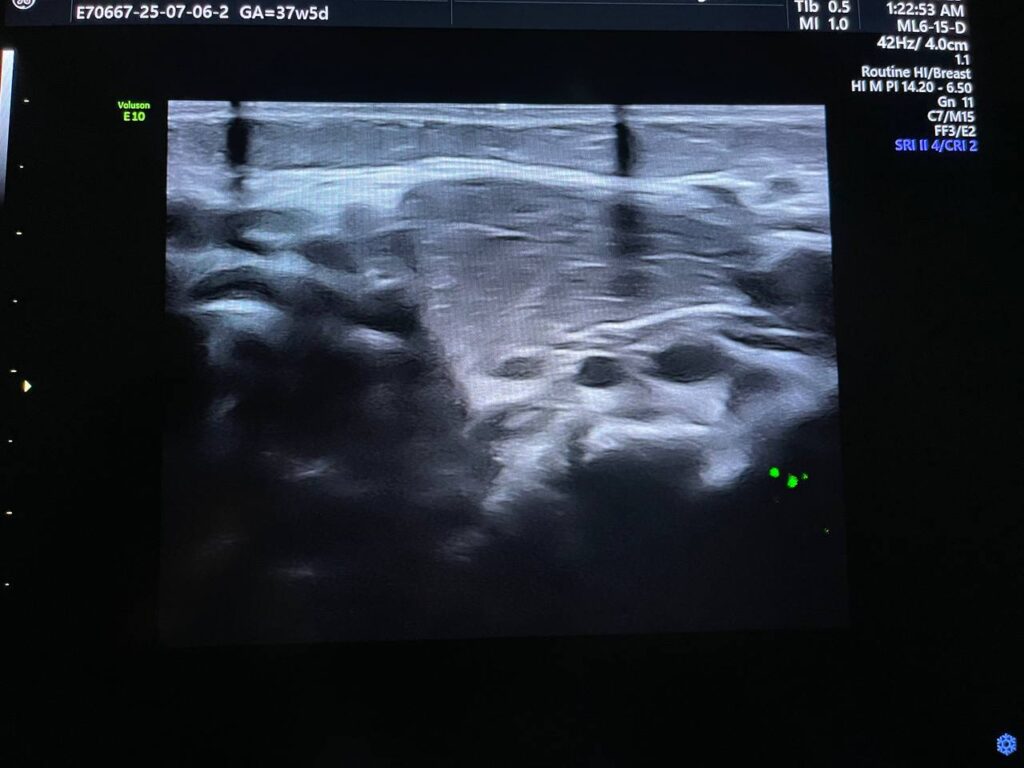

Presence of circumscribed soft solid mass, its size 26x14x27mm , inferior to the left sternocleidomastoid muscle , its vascular on color Doppler , could be ectopic thymus gland ?, others ? further study to exclude other pathology